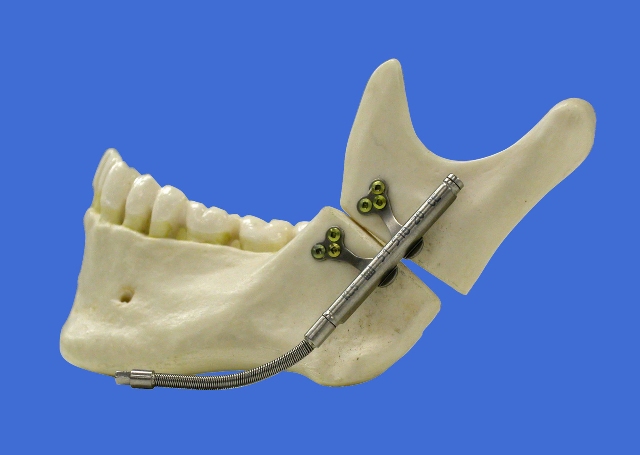

Pri takih stanjih je treba največkrat obrazne kosti na določenih mestih prelomiti, namestiti v pravilen položaj in nato učvrstiti. Ob tem lahko pri prekratkih delih kosti nastanejo vrzeli in podobno kot pri prirojenih nepravilnostih obraznega skeleta si lahko pomagamo s tako imenovano osteodistrakcijo, ki se v zadnjih petih letih izvaja tudi pri nas v Sloveniji. Gre za metodo, ki jo je prvi uporabil ruski kirurg Ilizarov že leta 1950, v maksilofacialni kirurgiji pa je v uporabi zadnjih 20 let. S posebno napravo (distraktorjem), ki se namesti na vsako stran kirurško prelomljenega dela kosti, se kost podaljšuje za približno 0,5 do 1 mm na dan. Na tak način se kost sproti dograjuje med obema odlomkoma in po dosegu želene dolžine in nekajtedenski imobilizaciji se distraktor odstrani, podaljšana kost pa je lahko povsem funkcionalna (slika 8).

Slika 8: distraktor nameščen za podaljševanje navpičnega kraka spodnje čeljusti